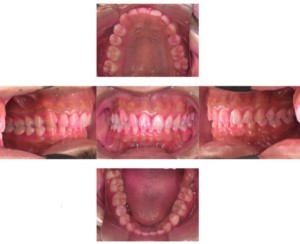

症例

症例1

Before

after

基本情報

年齢・性別 52歳・男性

主訴 主訴:久しぶりの歯医者なので歯石をとってほしい

治療部位:全顎

治療内容 1.歯磨き指導、歯肉縁上の歯石除去

2.歯磨きの確認、指導(磨けるようになるまで)

3.歯磨きの確認、指導、歯肉縁下の歯石除去(SRP)

4.PMTC

5.再評価、歯磨きの確認、指導

治療期間 1日

治療費 合計17,560円

・内訳

1、歯周基本検査・歯磨き指導、縁上スケーリング:1,800円

2、歯周精密検査・SRP(スケーリング・ルートプレーニング)、歯磨き指導:2,130円

3、SRP、歯磨き指導:3回(1,530円×3回)

4、PMTC、全顎再スケーリング、歯磨き指導:5,500円(自費診療)+1,260円

5、再評価(歯周精密検査)、歯磨き指導:2,280円

※PMTC以外、保険診療3割負担

(2023年5月現在現在)

リスク・副作用 ・毎日の歯磨きが不十分だと歯石を除去しても再度歯石がついてしまう

・最初は歯磨きのときに出血してくることがあるが、細菌が減って歯茎が引き締まってくると徐々に出血は落ち着いてくるため痛みがなければ辛抱強く磨いてもらう

・歯周病は時間をかけて静かに進行する病気なので、歯周病を治すにはそれなりに期間がかかる、すぐには治らない

・歯ぐきが引き締まると歯茎が下がり歯間に隙間ができる可能性がある

治療方針 一時的な治癒ではなく、将来的にこの治療が活かされるよう、患者さん自身である程度自己管理ができるようになることを目標とした

特記事項 ふつうのブラシと電動歯ブラシ使用(ブラウン丸型使)

歯間ブラシを1日1回は最低でも使って頂いた

担当者所見 あまり器用な方ではなかったため、決まったところがいつも磨けず奥歯に歯間ブラシがなかなか入れられませんでしたが、歯間ブラシのサイズを変えてみたり、内側から入れてみたりと試行錯誤してなんとかある程度磨けるようになりました。

その結果、出血が100%から7%へ激減することができました。

ただSRPをしただけではここまでの結果は出なかったと思います。

それほど日々のセルフケアが重要だということを再認識しました。

歯周ポケットが残っている部位、出血がある部位に関しては引き続き歯磨きを念入りに行なってもらう。